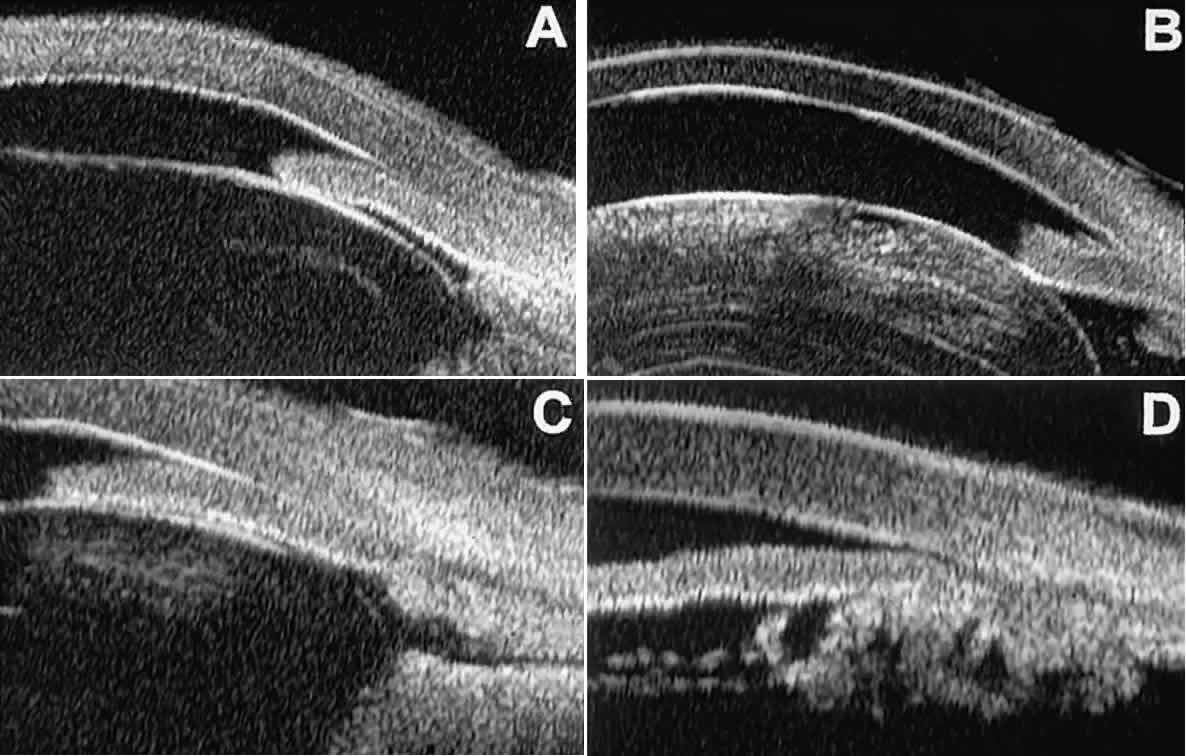

In most patients, the anterior segment can be evaluated thoroughly by slit lamp biomicroscopy unless the cornea is cloudy or opaque. In eyes with a cloudy or opaque cornea, UBM can be used to evaluate the cornea and to define the nature of underlying abnormalities in the angle, iris, ciliary body, lens, and anterior vitreous.4 For example, in eyes with severe congenital malformations of the anterior segment associated with a cloudy or opaque cornea (e.g., Peter's anomaly) (Fig. 14), UBM can be used to define the full extent of the abnormalities and thereby aid the clinician in deciding whether or not to consider any surgical intervention. UBM can also be used to study the extent of some clinically evident corneal abnormalities, such as corneal edema, bullous keratopathy, and band keratopathy (Fig. 15). In eyes with corneal edema (see Fig. 15A), UBM shows the epithelium to be thicker than normal and the stroma to have increased reflectivity. In bullous keratopathy (see Fig. 15B), UBM shows epithelial blisters of the cornea. In band keratopathy (see Fig. 15C), UBM shows superficial calcific deposits that are strongly reflective with shadowing of the underlying structures. In postinflammatory corneal scarring (see Fig. 15D), UBM can show the nonuniform cross-sectional corneal thickness and the presence or absence of a well-defined Descemet's membrane and endothelium layer.

Fig. 15. UBM features of miscellaneous corneal disorders. A. Corneal edema appears as thickening of superficial layer of cornea; corneal stroma is thinner than normal and abnormally bright. B. Bullous keratopathy appears as localized separation of corneal epithelium from Bowman's membrane filled with clear serous fluid. C. Band keratopathy appears as dense, brightly reflective subepithelial plaque in peripheral cornea. D. Postinflammatory corneal scarring after keratitis; note nonuniform corneal thickness and abnormal reflectivity of corneal stroma.